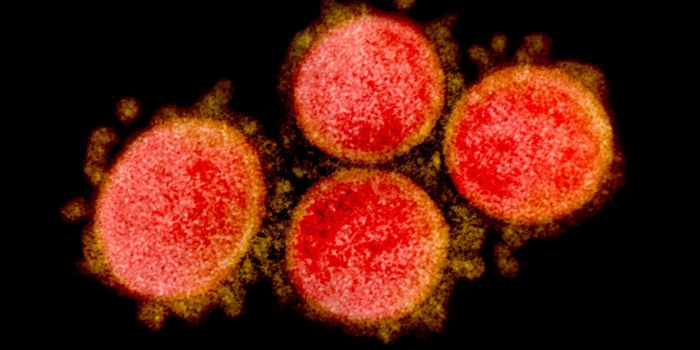

JAN 16, 2023ImmunologySARS-CoV-2, the virus that causes COVID-19 continues to cause huge numbers of infections around the world because of the ...

FEB 03, 2021ImmunologyResearchers are still studying how long a person can stay immune against COVID-19 following infection. A new study by a ...

MAY 14, 2020ImmunologyAntibodies are a powerful countermeasure against COVID-19. Not only can they relieve symptoms in patients experiencing s ...

NOV 06, 2020ImmunologyThe virus that causes COVID-19, SARS-CoV-2, uses its spike protein to gain access to cells, by binding to the ACE2 recep ...